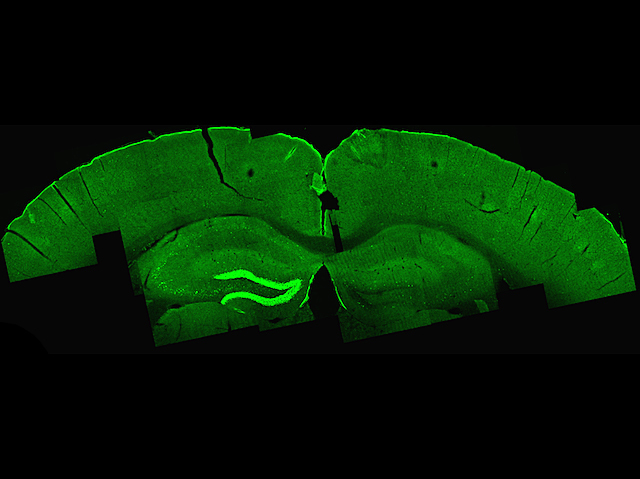

Patients with certain neurological disorders can achieve relief from their symptoms when appropriate parts of their brains are therapeutically activated. One approach – deep brain stimulation – is as invasive as it sounds, requiring patients to have holes drilled in their skulls and electrodes inserted. An alternative approach – transcranial magnetic stimulation – is entirely non-invasive, yet can only reach the brain’s outer-most layers, thus limiting the conditions it can treat. A new technique currently under development called temporally interfering (TI) stimulation may soon offer the best of both – deep brain stimulation without the surgery. The technique uses two ultrahigh electrical frequencies, which alone don't excite brain cells, passing straight through, but, when combined at a desired target location, interfere with each other and create a low-frequency signal to which neurons respond. Indeed, the image shows TI-induced activation (bright green) of neurons within a mouse’s hippocampus without stimulation of the surrounding brain.